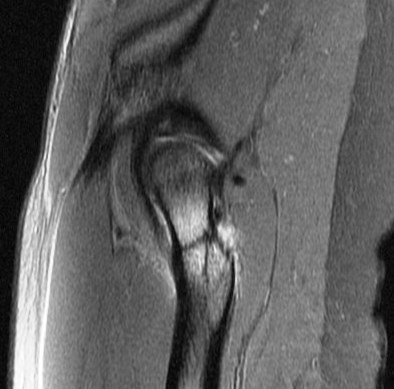

26 year old female police recruit. Pain during basic training.

Calcar stress fracture ( RID4695 )